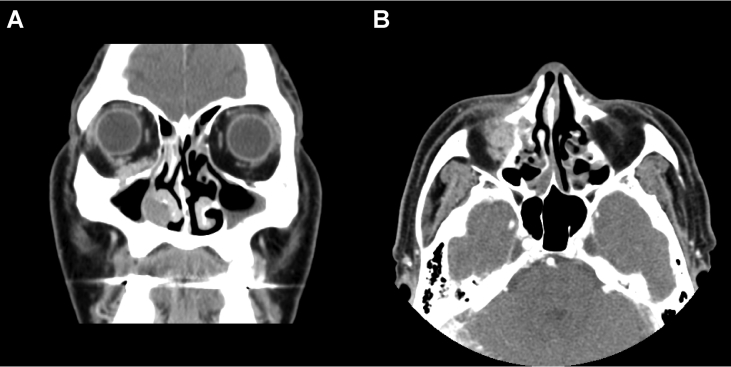

MRI with contrast enhancement showed a T2 intermediate enhancing mass extending from the right inferior extraconal space of the orbit to the right nasal cavity along the right nasolacrimal duct (Fig. 1). In-house computed tomography showed no significant interval change, but accentuated expansile bony change with destruction in the nasolacrimal duct when compared with MRI (Fig. 2). Positron emission tomography/computed tomography revealed no evidence of distant metastasis.

Fig. 2.

Computed tomography scan of the paranasal sinuses in the study patient. Infiltrating enhancing lesion involving right orbit, nasolacrimal duct and nasal cavity was shown in coronal section (A) and axial section (B). Destructive bony change is noted.